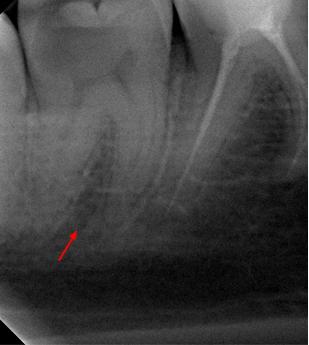

Пациентка 28 лет обратилась с жалобами на приступообразную ночную боль в области нижней челюсти справа.

На жевательной поверхности 47 зуба глубокая кариозная полость в пределах околопульпарного дентина, пульповая камера не вскрыта, зондирование болезненное, перкуссия безболезненная, холодовой тест резко болезненный, после удаления раздражителя болевая реакция продолжается в течении 20-ти секунд.

Диагноз: необратимый пульпит 47-го зуба.

На рентгенологических снимках представлена картина до лечения, диагностический снимок и конечный результат.